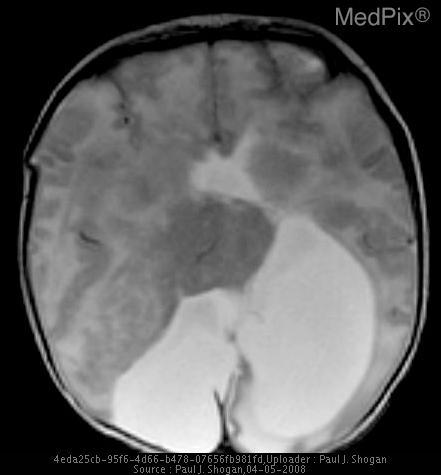

Given the following image:

Sample image from the MedPix dataset

And the prompt:

How does the interhemispheric fissure appear in this image?

Example Gemma 3 response:

The interhemispheric fissure appears as a dark streak, indicating significant tissue loss.

Example Gemma 3n response:

The interhemispheric fissure appears somewhat obscured by the fluid-filled mass.